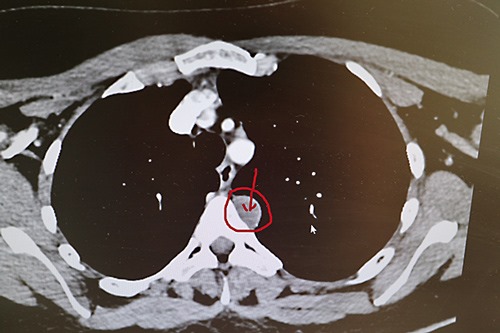

Muss sich mein Körper gedacht haben. Die Lymphknoten am Schulterblatt sind harmlos und unauffällig, aber als Zufallsbefund wurde “subpleural im Oberlappen links eine 14×22 mm messende Läsion” gefunden. Differentialdiagnostisch ist ein Schwannom (was für ein Wort) von BWK 4 zu denken und ein MRT der BWS wird empfohlen. Na denn. Termin hab ich in 4,5 Wochen, in Varel haben sie mir schon vor der Frage was denn gemacht werden muss gesagt, das sie im August sind terminlich.

Heute gelernt: da MRT- und CT-Bilder von unten aufgenommen werden, ist links rechts und rechts links. Hier also: Läsion an BWK 4 auf meiner linken Seite, die da eindeutig nicht hin gehört.